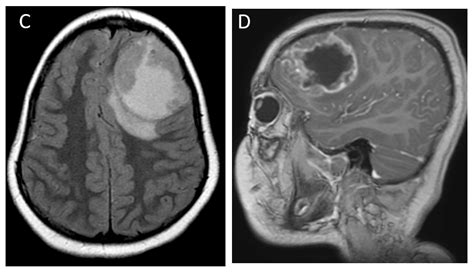

• Neurological Imaging: It is used to detect brain tumors, strokes, and other neurological conditions. The detailed images help neurologists identify abnormalities and plan treatment strategies.

Brain Tumors Detects abnormalities in the brain, including tumors, cysts, and other lesions.